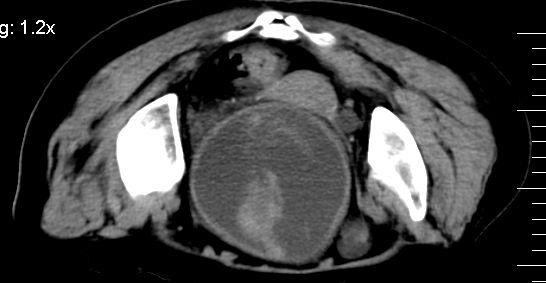

标题: CT10133:F、74岁,反复血尿10天。 [打印本页]

标题: CT10133:F、74岁,反复血尿10天。

补充一下,谢谢提醒!

1.膀胱后壁见不规则致密影,随体位改变,为膀胱内凝血块;

2.双侧输尿管下段扩张.输屎管结石可能大。建议作进一步检查。

双侧输尿管下端扩张,并膀胱内血凝块 输尿管下端结石

2.双侧输尿管下段扩张,临床有血尿病史,建议进一步检查,找出血原因。